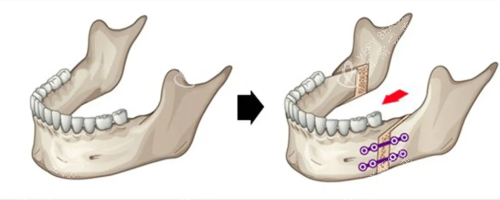

一、CBCT三维扫描:给骨头拍"3D电影",少看一眼都危险!

CBCT有多牛?它就像给骨头拍了部3D电影,能360度无死角显示:

上下颌骨的精细位置(误差<0.1mm)

牙根与神经管的"靠谱距离"

关节窝的形态是否正常

北京某综合医院口腔科主管张医师说:"没有CBCT就做正颌,相当于蒙眼开车。我们曾遇到患者CBCT显示双侧髁突不对称,及时调整了截骨方案,避免了术后张口受限。"

五、关节检查:别让"咔嗒"声毁了手术!

关节盘位置:是否移位

MRI是金标准,能清晰显示:

关节盘是否穿孔

骨面是否侵蚀

关节腔是否有积液